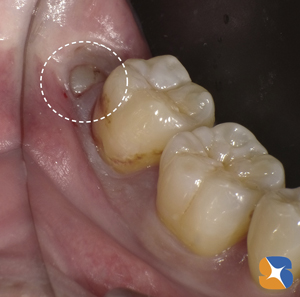

Dr:「歯茎に隠れてほとんど見えていませんが、本当に抜きますか?CT(保険適用)でも確認しますが、かなりの難抜歯になると思いますよ」

〈抜歯前〉この画像だけでは、下あごの骨の太い神経と智歯が交差しているように見えます。土曜日にしか手術が出来ないこの患者様は、

何処の医院へ行っても断られたそうです。